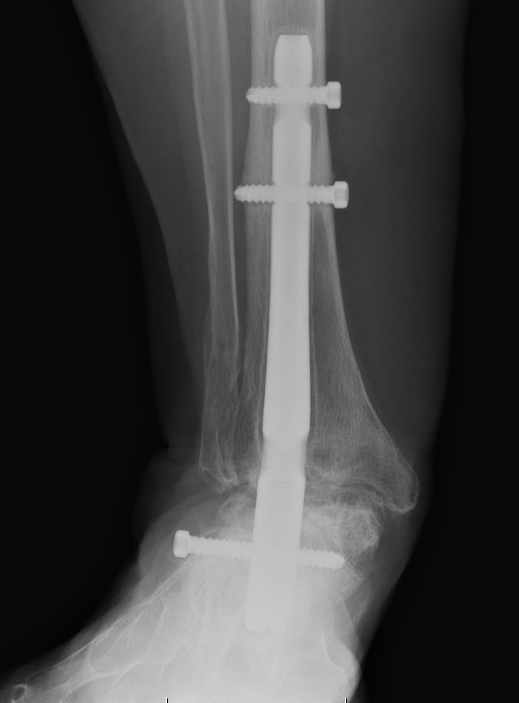

Stage 4 Tibialis posterior dysfunction

Hindfoot fusion

www.boneschool.com/pantalar-fusion